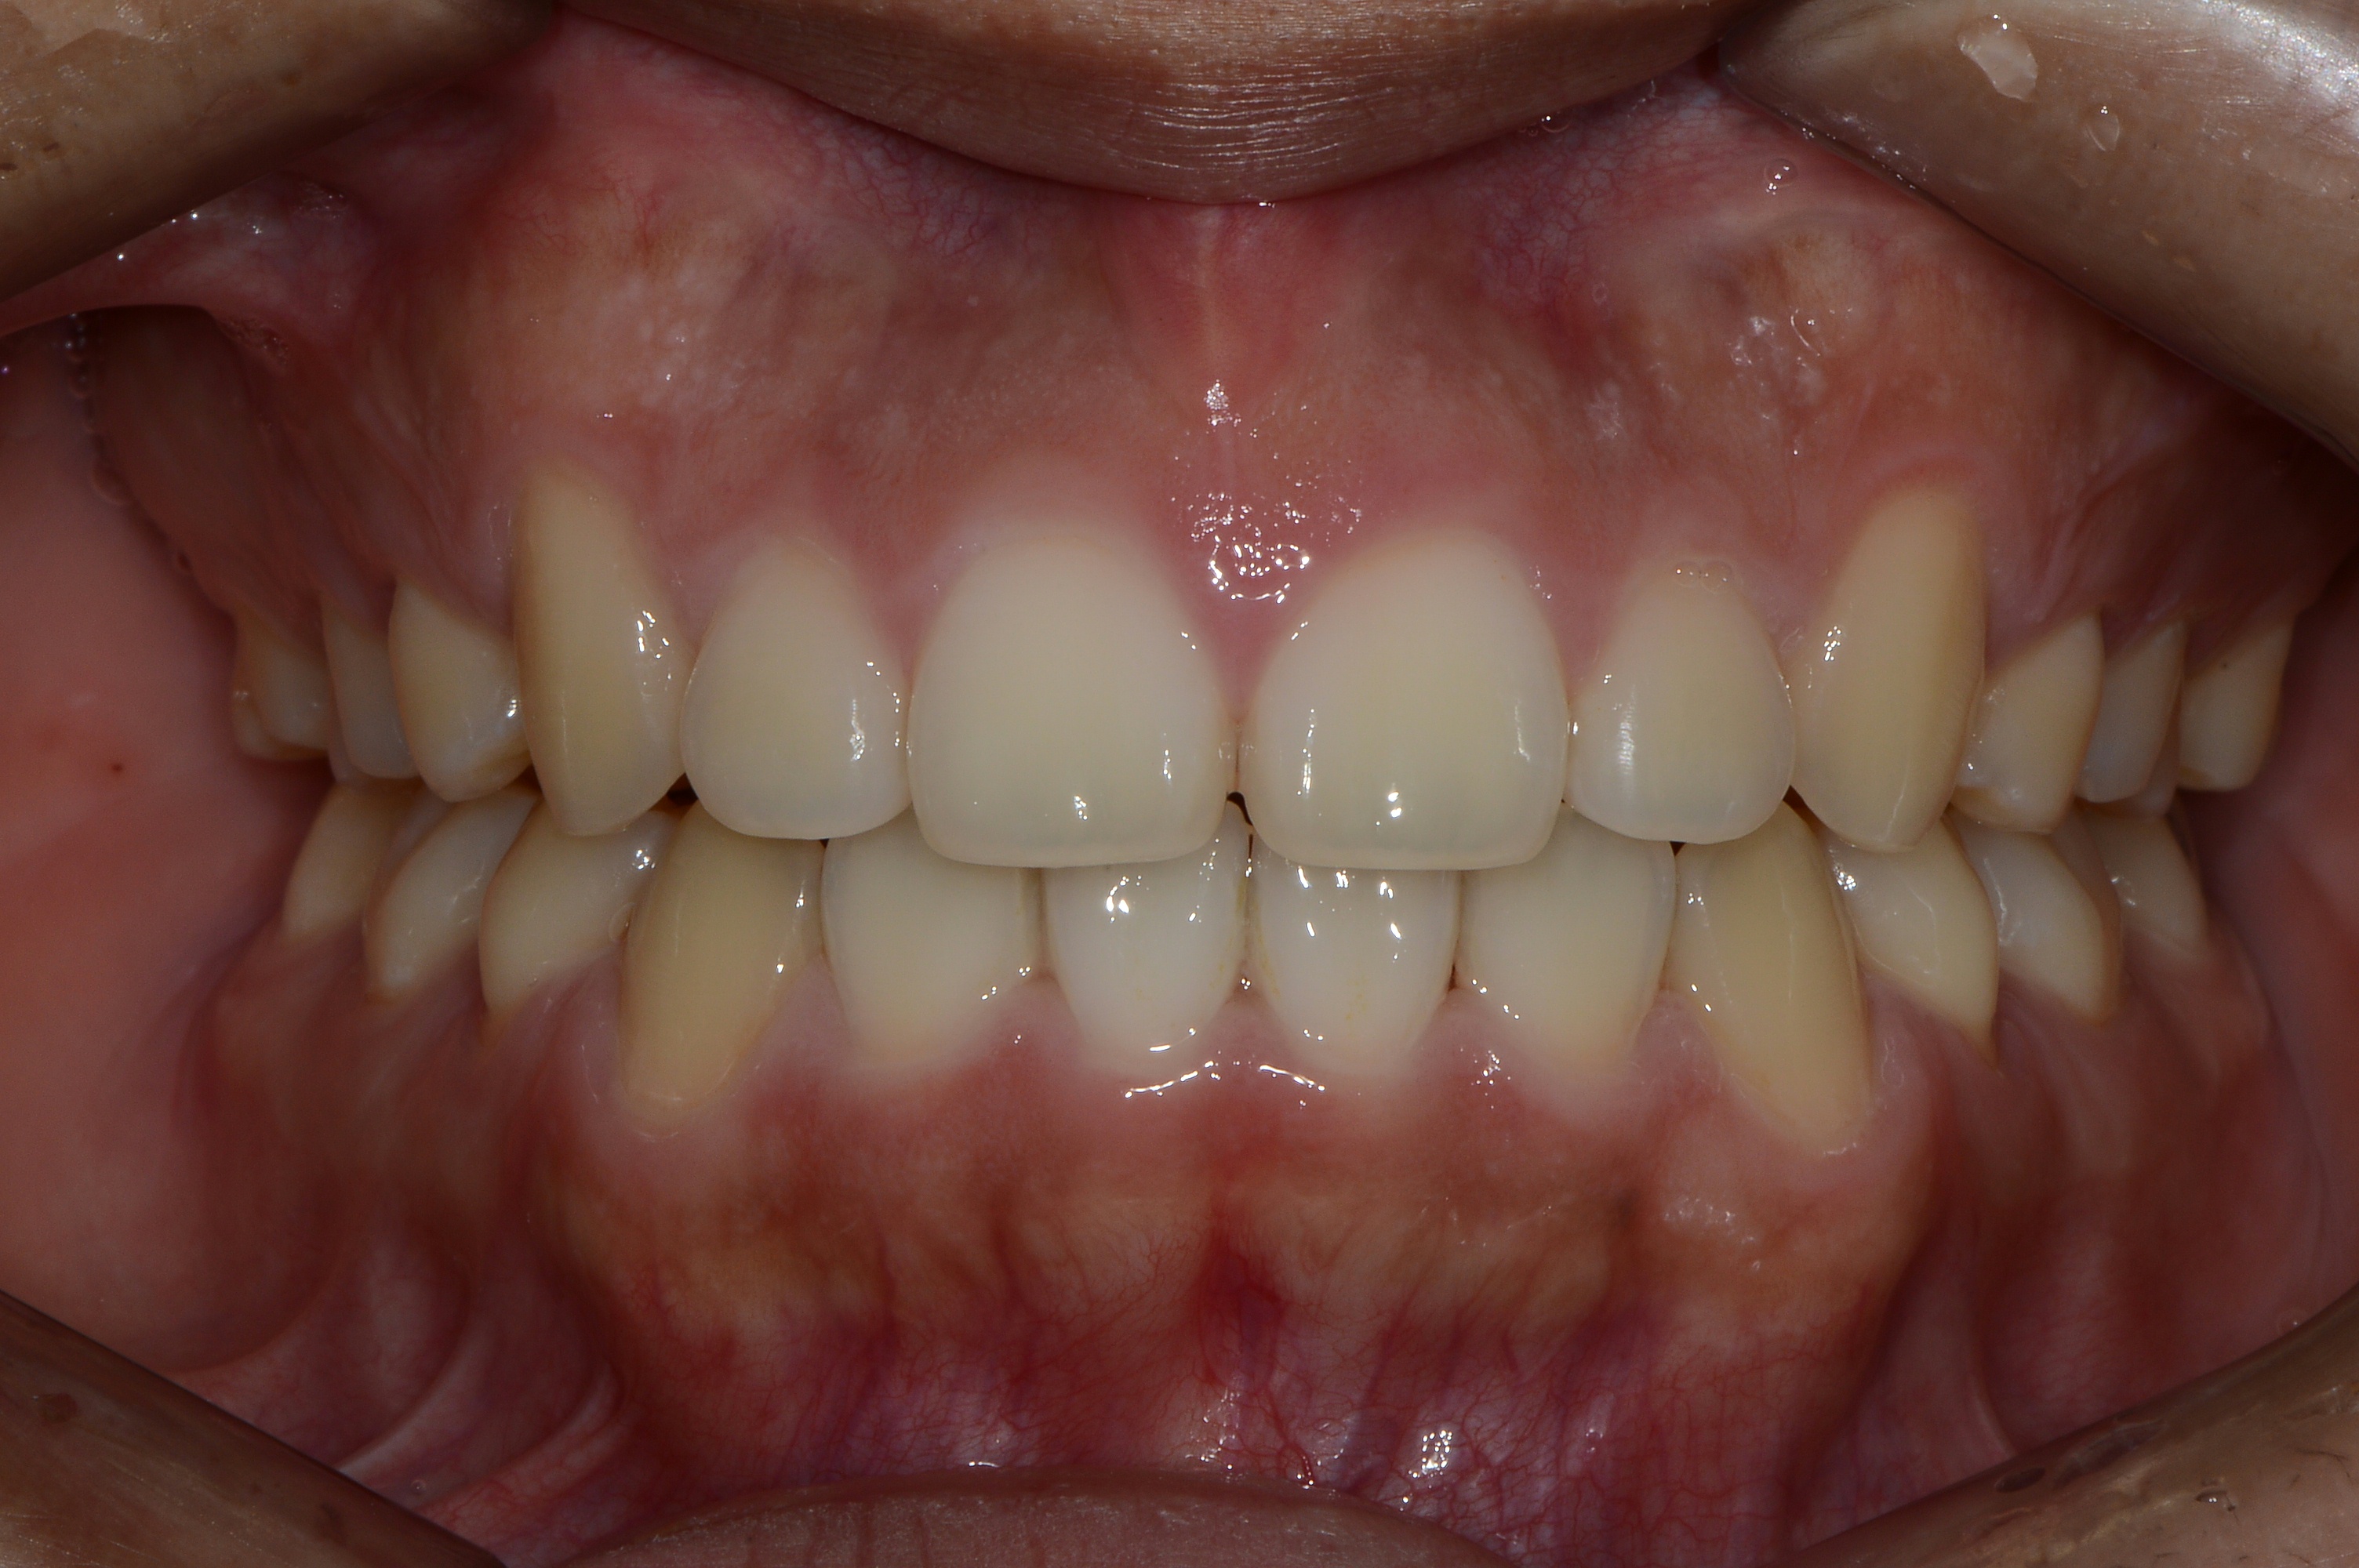

치료 후 사진입니다.